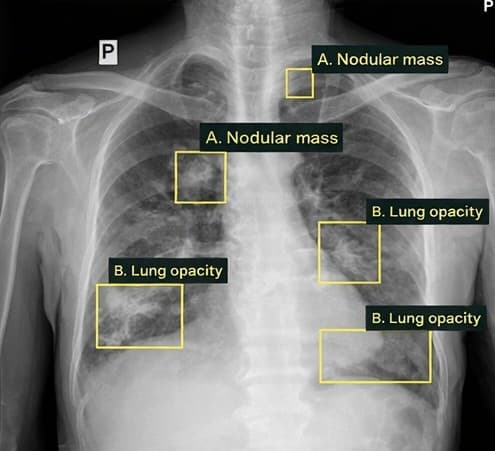

Tuberculosis